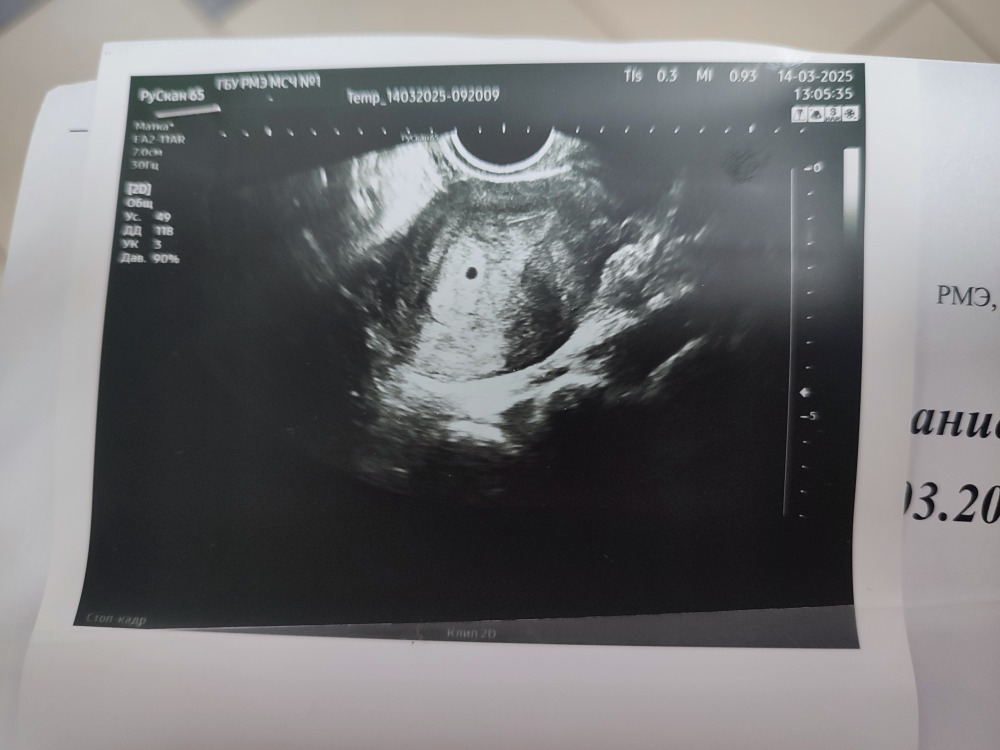

Медленный рост при стимуляции Первое узи!

21 ДПП, первое УЗИ